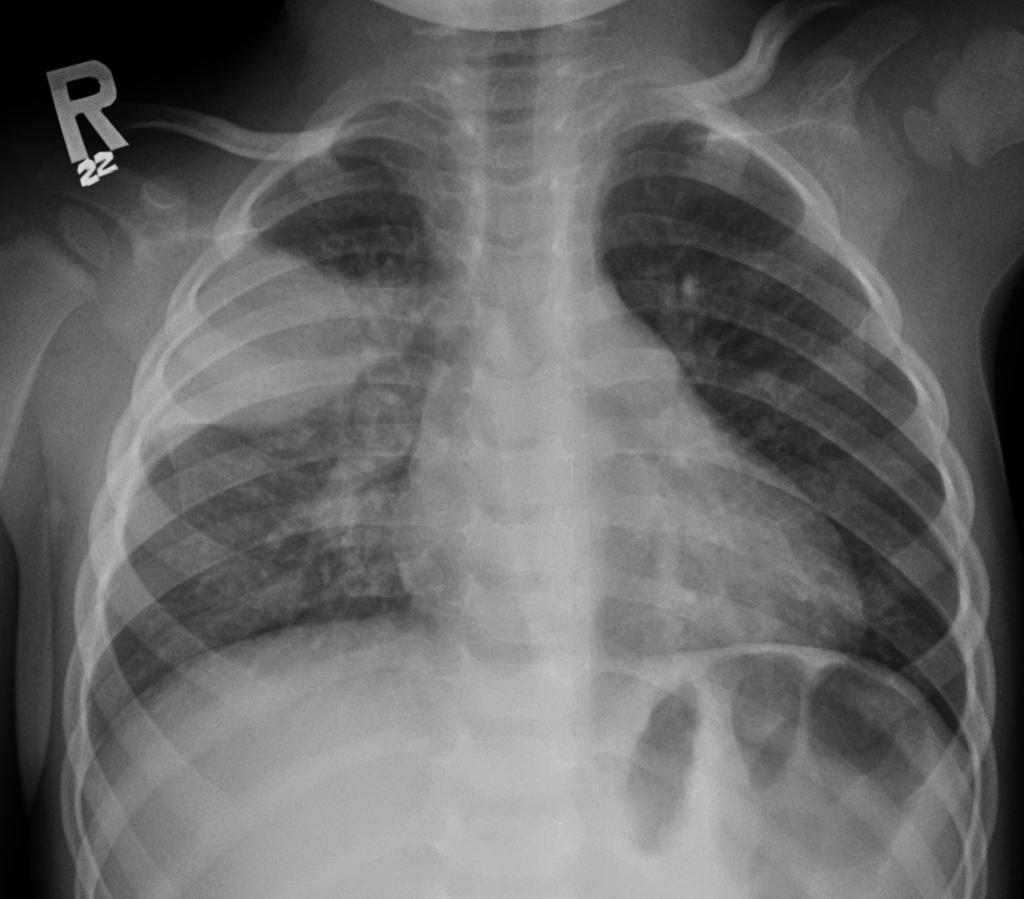

Анатомические изображения сегментов легких различных животных

Раздел: Другие животные